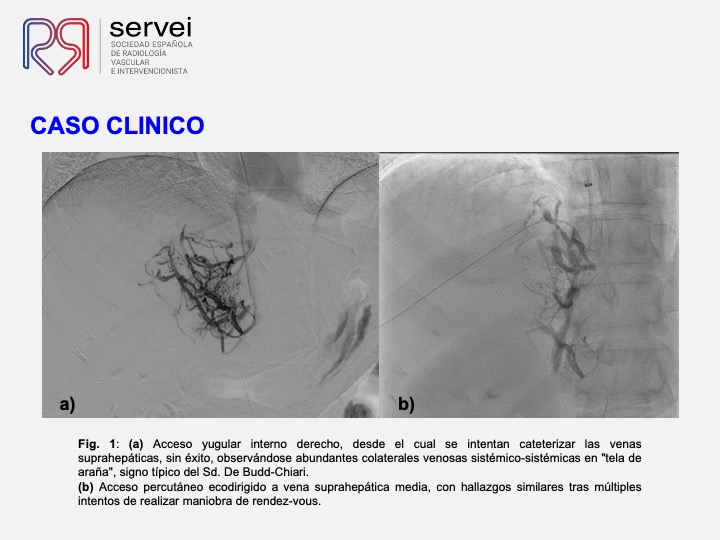

DIPS con técnica de “gun-sight”. Paciente con Síndrome de Budd-Chiari y eventual trombosis protésica